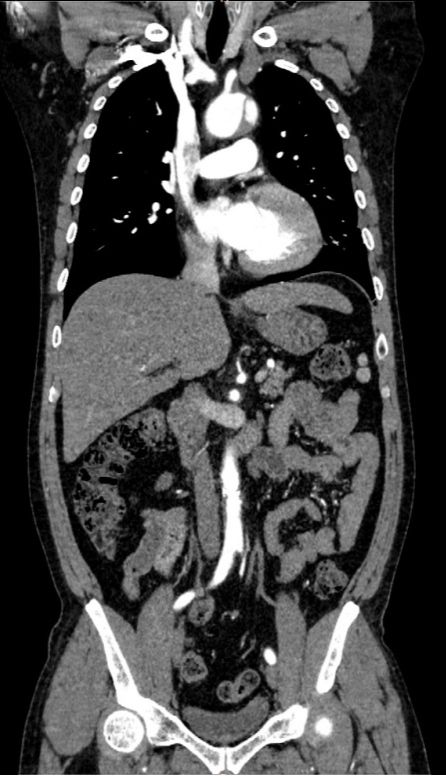

全身各部位血管造影:Incisive CT可以轻松实现大范围CT血管造影(CTA),准确了解血管及相关脏器的形态结构,评估血管及脏器功能,准确判断出血,栓塞、血管瘤、血管畸形、狭窄及肿瘤供血情况,为临床治疗提供极大帮助。

▲ 胸腹部CTA-主动脉夹层一目了然